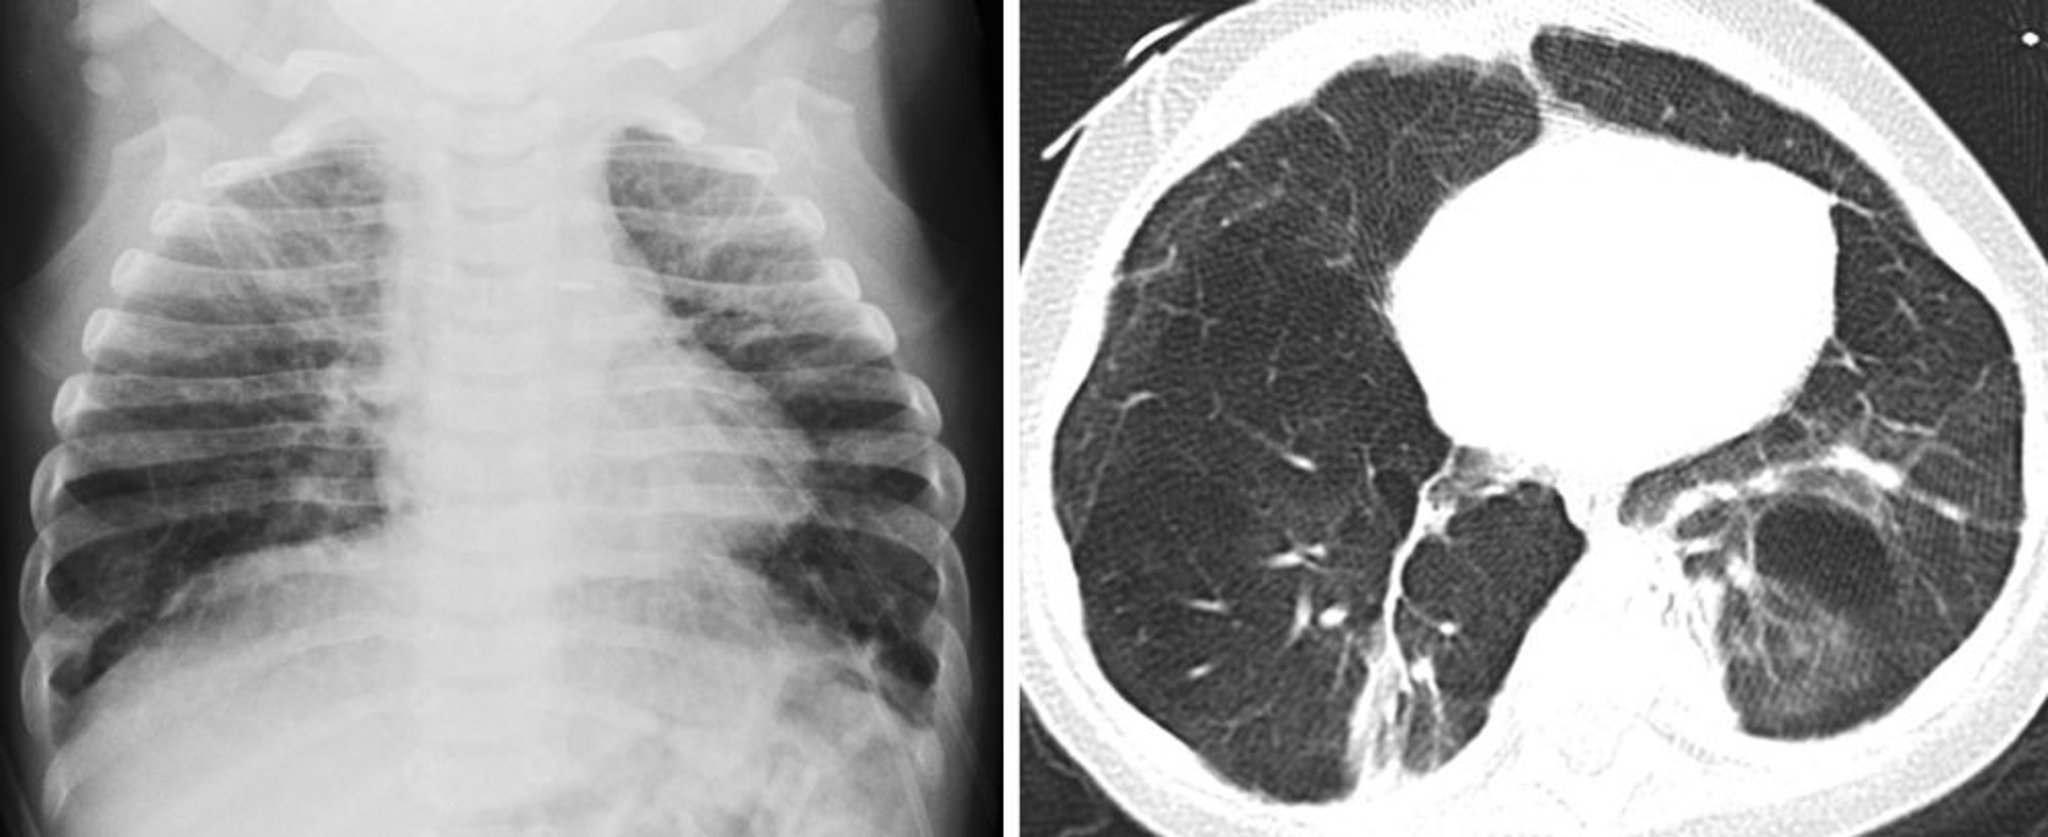

Displasia broncopolmonare (risultati di RX e TC)

Il bambino in queste immagini ha un'anamnesi di prematurità e displasia broncopolmonare. La radiografia frontale del torace sulla sinistra mostra opacità polmonari reticolari grossolane e iperinflazione in entrambi i polmoni. La TC mostra sulla destra opacità polmonari reticolari grossolane ed aerazione disordinata del polmone causata dalla fibrosi settale alveolare sottostante e da parenchima polmonare iperespanso.